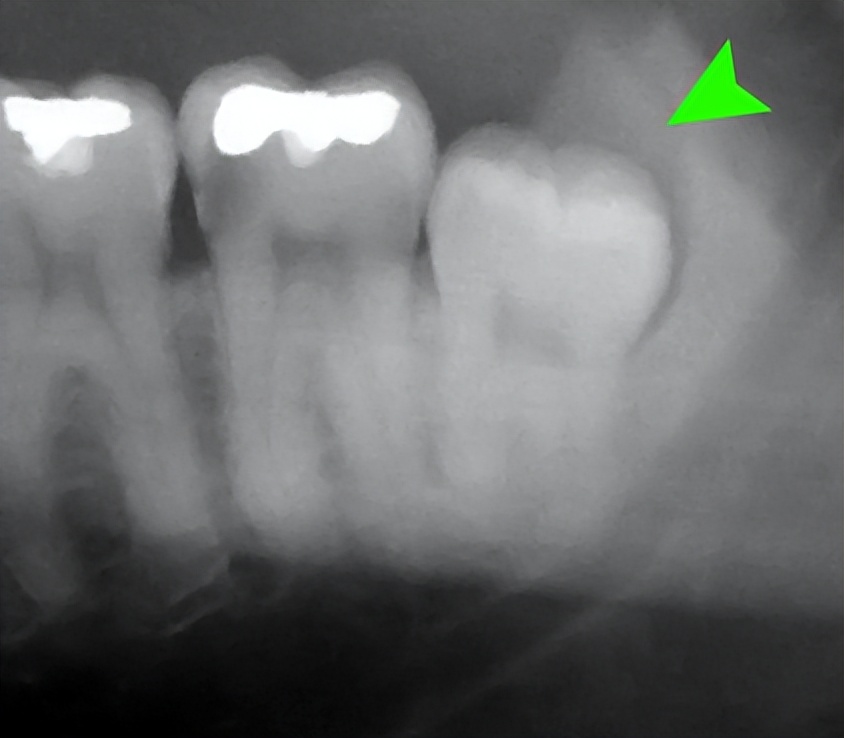

在过去的一百多年中,人类的食物进一步精化,对咀嚼的要求进一步降低, 智齿(第3臼齿,即离门齿最远的牙齿)的重要性也越来越低。 加上智齿在口腔最里面,难以清洁,常常和邻近臼齿一起,成为最容易长牙周炎和龋齿的地方。同时,人类在演化过程中,脸部变小,容纳智齿的空间也越来越小,成长时容易发生异位,影响旁边的臼齿发育。

智齿的生长往往会挤压到其他臼齿,造成牙疼,本图绿色箭头处即为智齿 图片来源:wikipedia